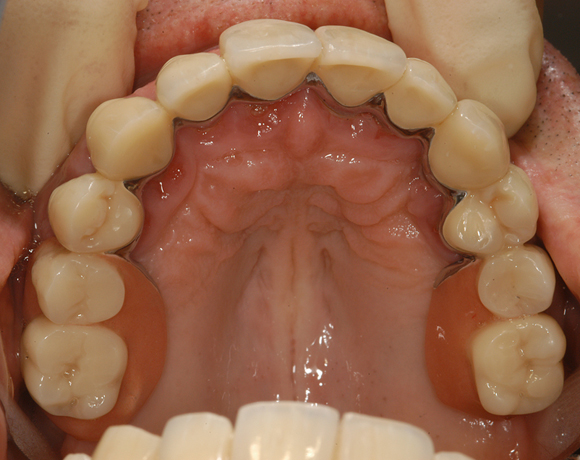

Üblicherweise werden Teleskopkronen aus Metalllegierungen hergestellt. Der Nachteil dieser Prothesenkonstruktion für den Patienten ist, wenn er seine Prothese aus dem Mund nimmt sieht man nur noch gold- oder silberfarbene Zahnstümpfe. Mit den Innenteleskopen aus e.max Press sieht man zahnfarbene Stümpfe, die unserem ästhetisches Verständnis nicht gleich ins Auge stechen.

Im vorliegenden Patientenfall musste eine komplette Neukonstruktion der Oberkieferversorgung vorgenommen werden, da auf Grund parodontaler Probleme die Seitenzahnbrücken 15 – 17 und 25 – 27 nicht mehr zu halten waren. Die verbliebenen acht Frontzähne bzw. Prämolaren waren auch parodontal vorgeschädigt und es war ungewiss wie lange sie einzelne noch halten lassen. Um nicht bei jedem Verlust eines der Restzähne eine Neukonstruktion zu brauchen, hat man sich für eine Teleskopprothese entschieden. Für den Patienten war es allerdings nicht vorstellbar goldfarbene Primärteile im Mund zu haben, so wurde der Versuch unternommen diese aus e.max Press und Galvano Sekundärteilen herzustellen.